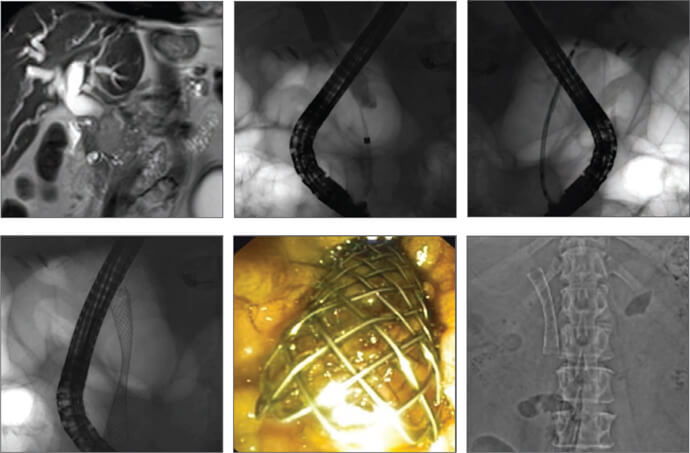

Case 1

An 87-year-old patient admitted with obstructive jaundice associated with inoperable pancreatic cancer. A malignant stricture (about 3 cm in length) was located in the distal part of the common bile duct (CBD). After sphincterotomy, a 60 mm Cook Evolution Biliary uncovered stent was deployed over the guide wire with immediate drainage of black bile.

Case 2

A 63-year-old patient was admitted with obstructive jaundice. CT and MRI showed pancreatic head mass with hepatic metastasis. In cholangiogram we observed 2 stenoses in CBD (hilar and distal segment). We used the 80 mm Evolution Biliary uncovered stent with resolution of both stenoses.